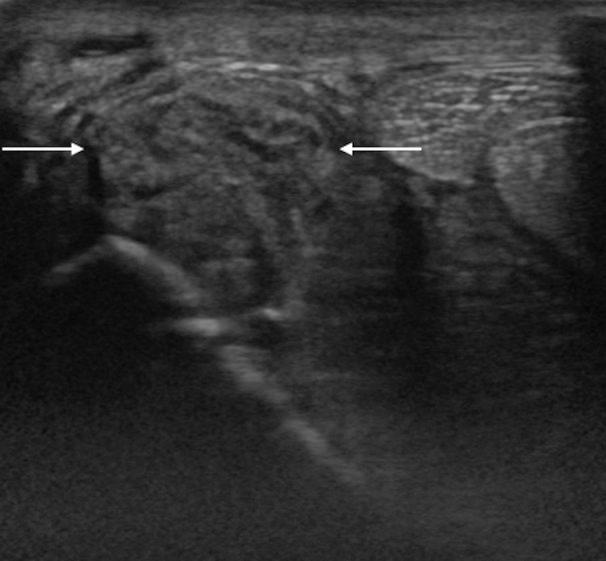

Desmitis of the oblique distal sesamoidean ligaments (ODSL) is caused by hyperextension of the metacarpophalangeal/metatarsophalangeal joint and has been described as a significant cause of lameness in racehorses. In this study, three Thoroughbred racehorses (age range: 3-6 years) were diagnosed with desmitis of the forelimb ODSL using standing low-field magnetic resonance imaging (sMRI). Radiography and ultrasonography were inconclusive with regard to a definitive diagnosis. For all horses, the sMRI characteristics included increased signal intensity within the medial ODSL on T1-weighted gradient echo, T2-weighted fast spin echo and short tau inversion recovery fast spin echo images, which use a fat suppression technique. Effusion of the digital flexor tendon sheath was also clearly visible on sMRI. Following rest and controlled exercise for roughly 3 months, two horses successfully returned to racing within 5 months. Our findings support the use of sMRI for diagnosing ODSL injuries in Thoroughbred racehorses.

斜方远籽骨韧带(ODSL)炎是由掌指关节/跖趾关节过度伸展引起的,已被描述为赛马跛行的一个重要原因。在本研究中,使用站立式低场磁共振成像(sMRI)对3匹纯种赛马(年龄范围:3至6岁)进行了前肢ODSL炎的诊断。X线摄影和超声检查对于明确诊断尚无定论。对于所有马匹,sMRI特征包括在使用脂肪抑制技术的T1加权梯度回波、T2加权快速自旋回波和短tau反转恢复快速自旋回波图像上,内侧ODSL内信号强度增加。在sMRI上也清晰可见指屈肌腱鞘积液。经过大约3个月的休息和控制运动后,两匹马在5个月内成功重返赛场。我们的研究结果支持使用sMRI诊断纯种赛马的ODSL损伤。